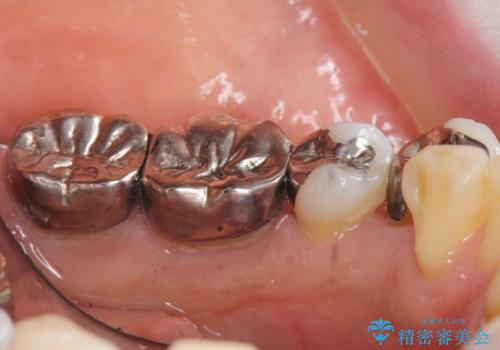

精査したところ、左下の小臼歯(左下5)の銀の詰め物の下に大きなう蝕を認めました。

またその手前の歯(左下4)は頬側転位していることを気にされておりました。

矯正をおすすめしましたが希望されず、最小限の方法で虫歯と歯並びを治したいとのことでした。

患者様のご希望により、セラミッククラウンにより可及的にう蝕除去後の補綴及び歯並びの改善を行いました。